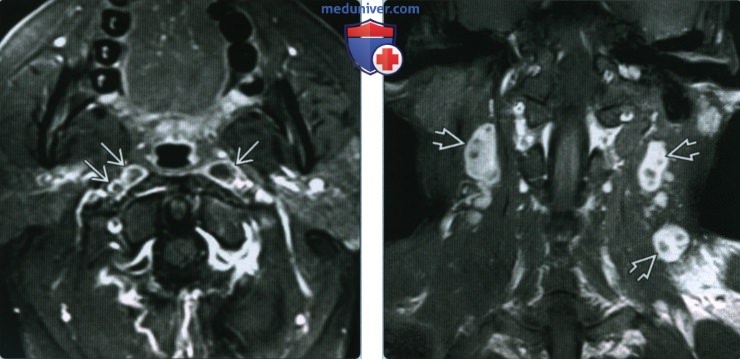

Мезентериальные лимфатические узлы: УЗИ и диагностика